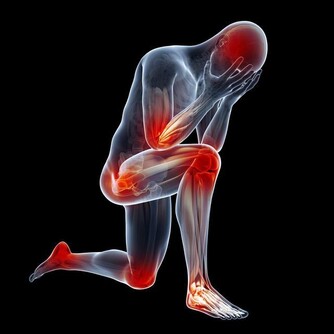

除了體溫升高,發燒還往往伴隨感覺冷、皮膚發紅發燙、頭痛、身體痛、疲勞虛弱、食慾不振、心率加快、脫水等症狀。